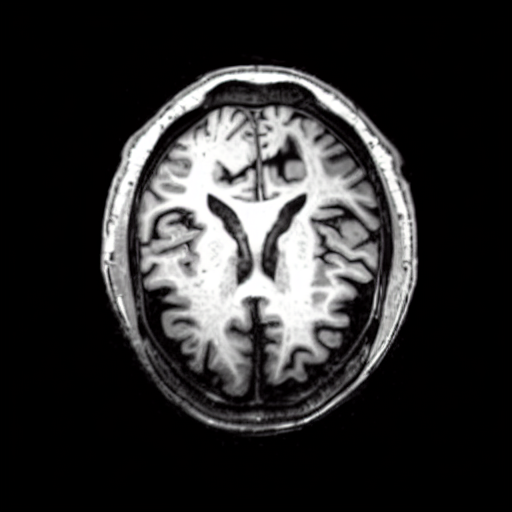

We present the results of conditional medical image generation with and without our proposed method LD, in Tab. 1, and Fig. 5. In Fig. 4, we show examples of brain MR images generated by the different methods combined with LD for two different classes of cognitively normal (CN) and Alzheimer’s disease (AD). The results were obtained by fine-tuning the corresponding method on the medical data with LD. As shown in Fig. 4, the samples generated through Custom Diffusion tuning are realistically looking while understanding the difference between CN and AD brain properly, which other methods failed at. Textual inversion seems to understand the concept but fails to understand the brain structure properly. Quantitative results on the performance of all our methods are presented in Tab. 1. Qualitative results on the CheXpert [19] dataset, along with a user study and ablation of different parameters, optimization algorithm, and more, are included in the supplementary material.

Qualitatively, Fig. 5 shows a significant improvement of the visual realism across all methods when using a drift of . The background is consistently black as in real brain MR images; the shape of the brain becomes more realistic, and the white and gray matter structure improves. For an analytical evaluation, we calculated the FID between our test data and 200 synthetically generated images from each method (100 CN, 100 AD). The results in Tab. 1 demonstrate that LD improves the ability of the model to generate realistic MRI slices for both healthy brains and brains with Alzheimer’s disease. For this reason, all following experiments were done with LD.